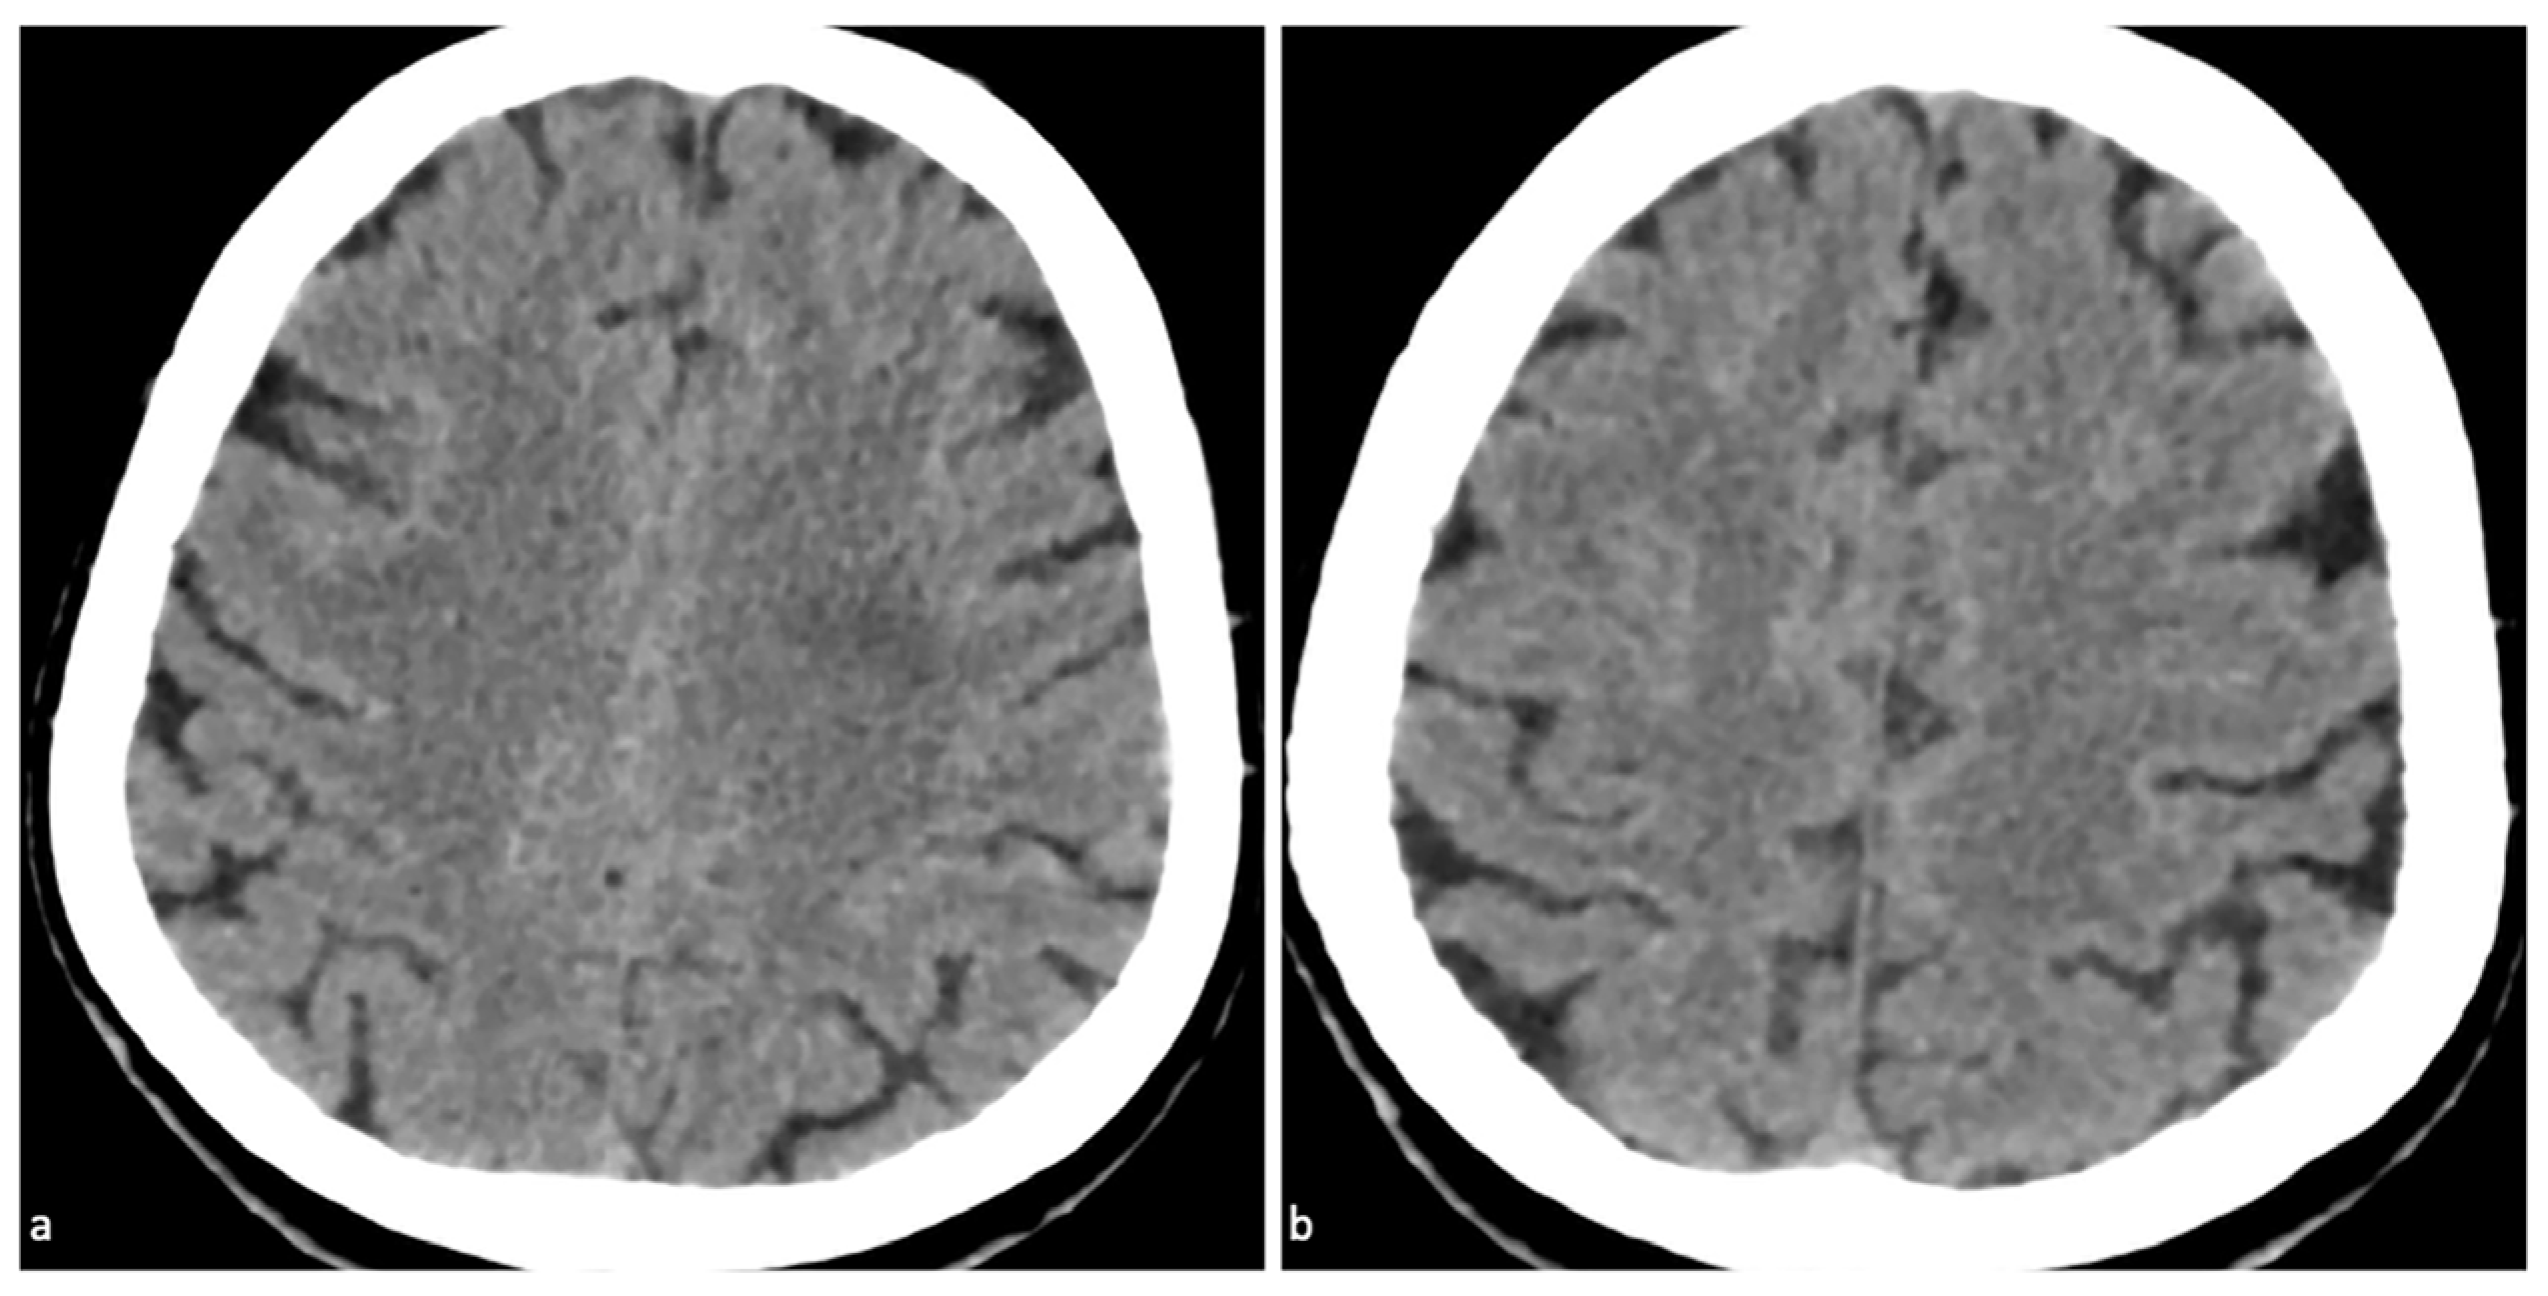

Dual-Energy Computed Tomography (DECT) for Diagnosing Contrast-Induced Encephalopathy (CIE) Mimicking Intracranial Hemorrhage (ICH): A Rare Case

Shen, Y.; Ye, T. Dual-Energy Computed Tomography (DECT) for Diagnosing Contrast-Induced Encephalopathy (CIE) Mimicking Intracranial Hemorrhage (ICH): A Rare Case. Diagnostics 2025, 15, 2426. https://doi.org/10.3390/diagnostics15192426